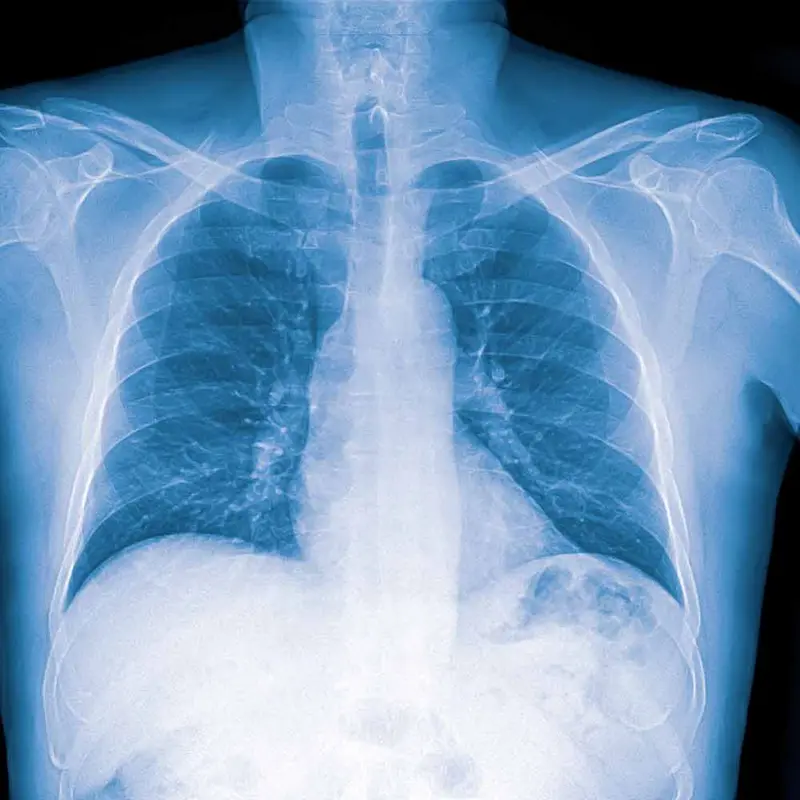

Røntgenbilde av lunger med lungebetennelse

Lungebetennelse kan ses som et hvitt område på røntgenbilde av lungene.